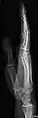

• Radius and Ulna - AP and Lateral

• Fingers - DP and Lateral